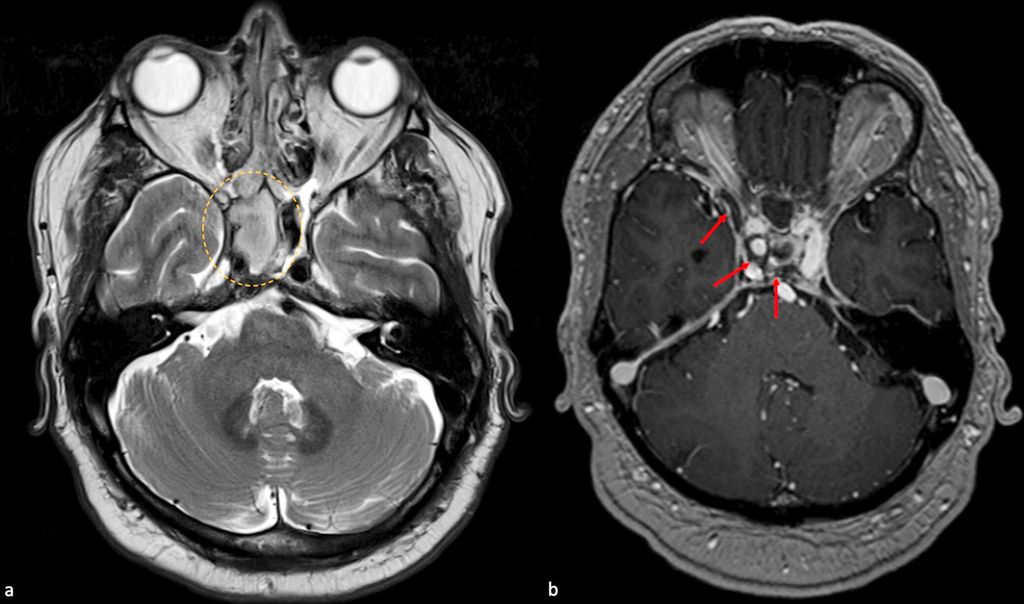

Abb. 3: 61-jähriger männlicher Patient mit Sinus-cavernosus-Thrombose. Der Patient stellte sich mit Kopfschmerzen, tränenden Augen und erhöhten infektiösen Parametern vor. Es wurde eine MRT durchgeführt, die eine Sinusitis zeigte (oranger Kreis in a). Die kontrastmittelverstärkte T1-Aufnahme (b) zeigte Füllungsdefekte im Sinus cavernosus sowie im Sinus sphenoparietalis (rote Pfeile)

Ein seltenes, aber typisches klinisches Bild ist die Assoziation einer ipsilateralen Ptosis, Chemosis, Ophthalmoplegie, von sensorischen Defiziten des ophthalmischen und maxillären Astes des 5. Hirnnervs und Kopfschmerzen, die mit einer Thrombose des Sinus cavernosus einhergehen (Abb. 3).